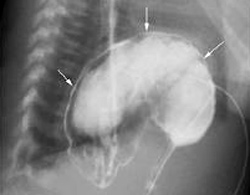

Thay vì nằm ở ổ bụng, dạ dày của bệnh nhi 7 tuổi (Bà Rịa - Vũng Tàu) lại chui lên lồng ngực. Đây là bệnh lý xoắn dạ dày ở thể rất hiếm gặp bởi thường chỉ xảy ra ở trẻ lớn hơn.

Dạ dày chui lên lồng ngực bệnh nhân. Ảnh: B.V

Tại bệnh viện, diễn tiến của bé ngày càng xấu, bụng trướng to, ói nhiều hơn. Chẩn đoán qua hình ảnh cho thấy có hiện tượng dạ dày dãn to, ứ đọng dịch. Kết quả chụp phim còn phát hiện, dạ dày của bé phần dưới bị xoắn lên cao và một phần chui lên lồng ngực.

Bệnh nhân lập tức được mổ nội soi để đưa dạ dày trở về ổ bụng và khâu cố định đề phòng tái xoắn lại. Các bác sĩ cũng khâu hẹp lỗ thoát vị nơi dạ dày chui lên.

Theo các bác sĩ chuyên khoa ngoại Bệnh viện Nhi Đồng 2, xoắn dạ dày ở trẻ em khá hiếm gặp và trường hợp này còn hiếm hơn bởi những ca khác thường trên 10 tuổi.

Đến nay, y văn thế giới ghi nhận được khoảng 160 ca và biểu hiện thường gặp là đau bụng đột ngột, ói nhiều và liên tục. Một số trường hợp bé có thể suy hô hấp cấp kèm theo tím tay chân do đau. Bệnh có thể nguy hiểm đến tính mạng của bé nếu không được chẩn đoán và can thiệp kịp thời.